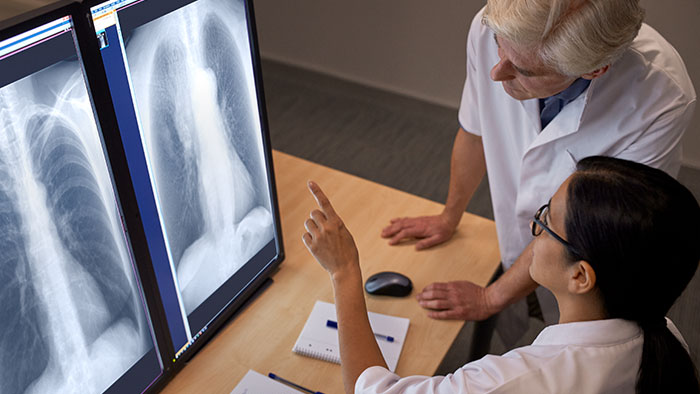

Die Röntgen- und Fluoroskopiesysteme von Philips bieten exzellente Arbeitsabläufe und qualitativ hochwertige Bilder. Sie sorgen so für einen hohen Durchsatz und Diagnosesicherheit sowie für eine hohe Mitarbeiter- und Patientenzufriedenheit. Gemeinsam können wir alles erreichen. Gesundheit kennt heutzutage keine Grenzen und gleiches sollte auch für Gesundheitsversorgung gelten.

Digitale Radiographie